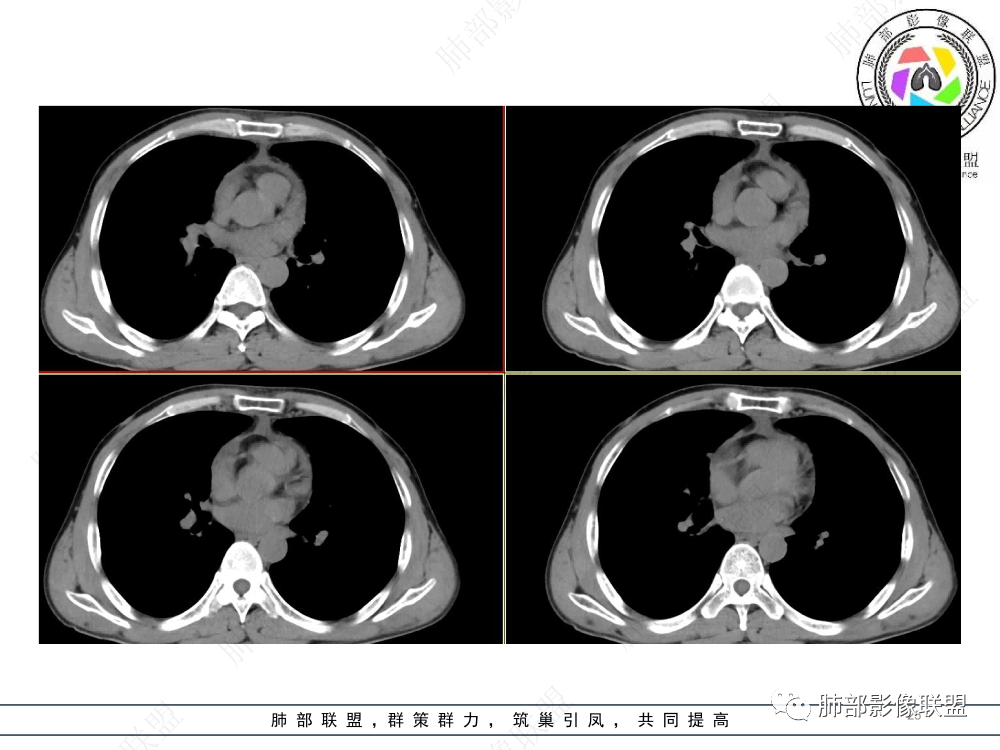

1.临床资料:中老年男性,病史较长-8个月,主诉胸痛,实验室资料:乳酸脱氢酶(LDH)升高。

2.影像表现:前上纵隔较大肿块,密度不均,形态不规则,边界不清,有结节样突起,脂肪间隙显示不清。病灶侵犯左无名静脉及上腔静脉,其中左无名静脉闭塞(胸背部侧支循环明显,亦表明回流受阻)。增强后轻中度不均强化。坏死边界欠清晰。可见心包积液,提示心包受侵犯。右侧上叶及纵隔胸膜下结节影,疑胸膜肺转移可能。胸骨柄后缘皮质不完整,疑骨质破坏(未提供骨窗及矢状位图像)。左锁骨上可见肿大淋巴结。